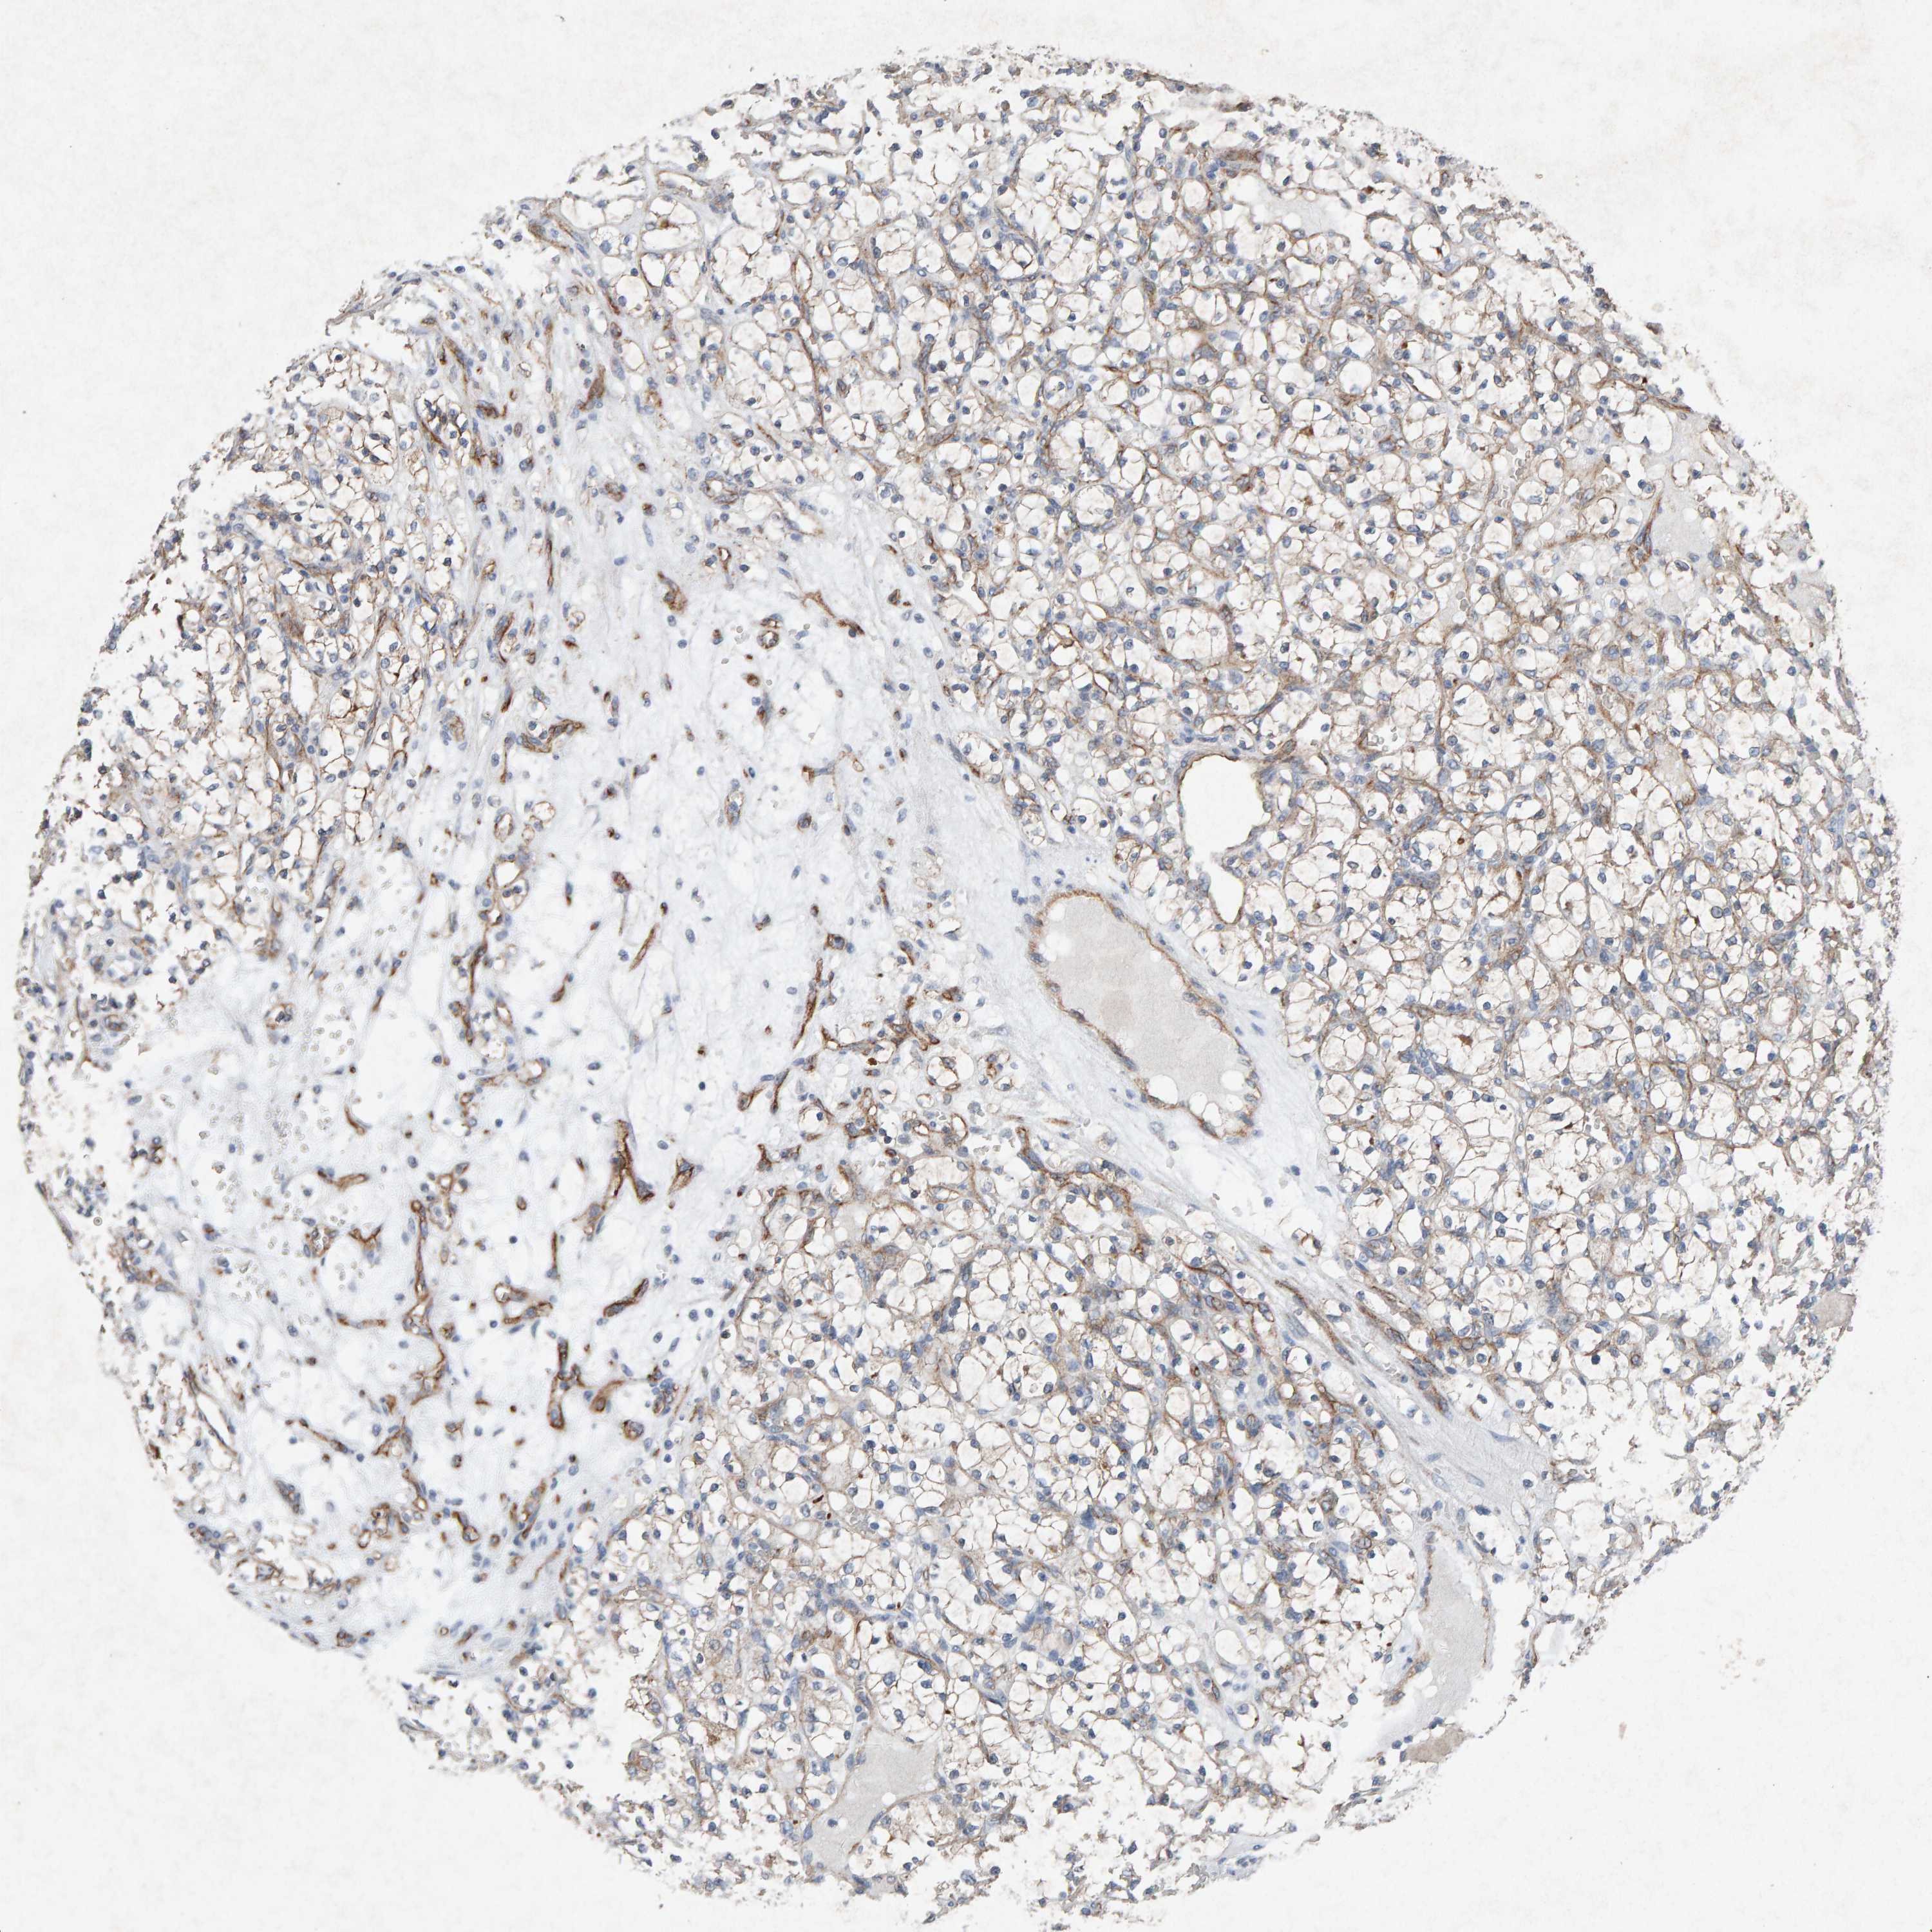

PTPRM is validated prognostic, high expression is favorable in Kidney Renal Clear Cell Carcinoma (validation)

Stage:

Survival analysis

Best expression cut offi

Based on the FPKM value of each gene, patients were classified into two groups and association between prognosis (survival) and gene expression (FPKM) was examined. The best expression cut-off refers the FPKM value that yields maximal difference with regard to survival between the two groups at the lowest log-rank P-value. Best expression cut-off was selected based on survival analysis .

When clicking on this number, the vertical dashed line indicating cut-off, the interactive survival plot, and the Kaplan-Meier curve will be adjusted to show results based on the best expression cut-off.

: 78.72

Average pTPM 78.8

Number of samples 100